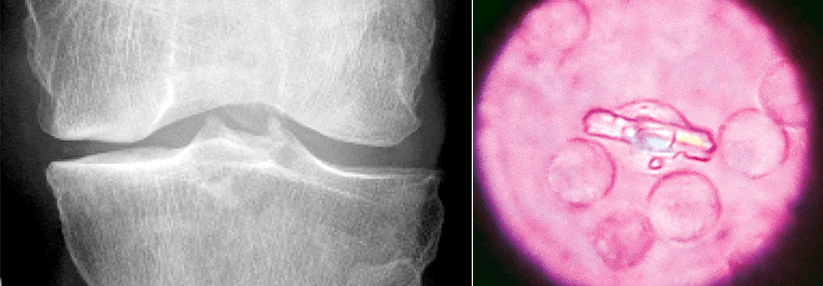

Durch das rheumatische Fieber

kann es zum Beispiel zu einer Stenose

der Mitralklappe kommen. Durch das rheumatische Fieber kann es zum Beispiel zu einer Stenose der Mitralklappe kommen. © iStock.com/ChaNaWiT; wikimedia/CDC